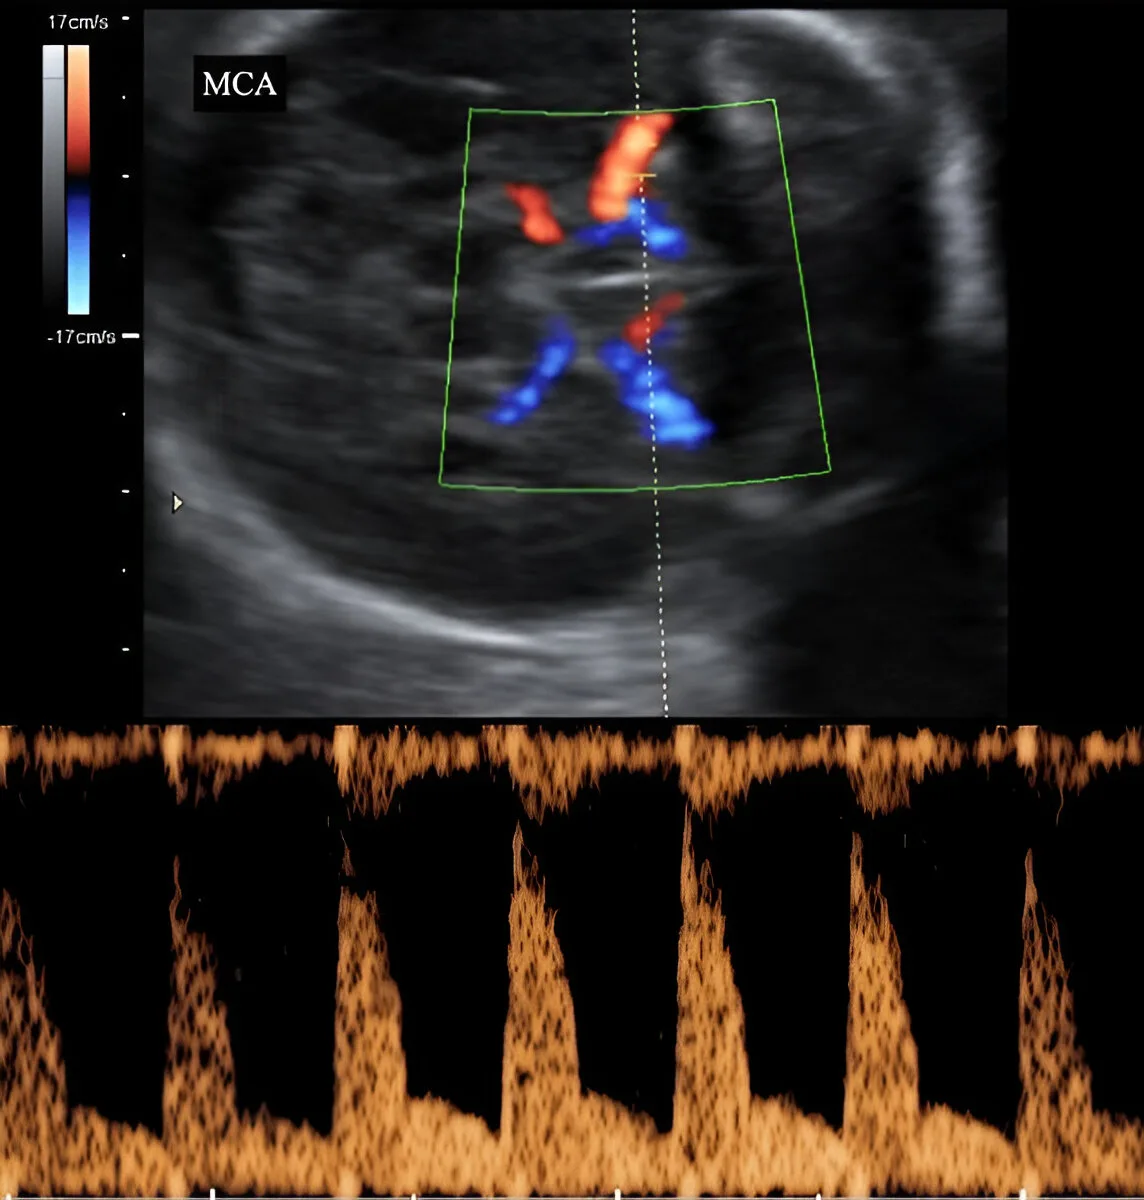

MCA Doppler – Fetal Brain Blood Flow Evaluation

At Henotic Diagnostics, our experienced female radiologists ensure comfort and precision. Indeed, every pregnancy scan follows ISUOG protocols and NABL-accredited standards. Additionally, we specialize in 3D Uterine Artery Doppler, 3D Umbilical Artery Doppler, 3D MCA Doppler, and 3D Ductus Venosus Doppler in Kharghar & Navi Mumbai. Similarly, we provide Uterine Artery Doppler, Umbilical Artery Doppler, MCA Doppler, Placental Doppler, and 3D Power Doppler Angiography in Kharghar & Navi Mumbai. Not only does this ensure accurate monitoring of fetal oxygen flow, but also precise maternal blood supply assessment. Additionally, we offer affordable, expert Obstetrics (OBS) Doppler in Kharghar & Navi Mumbai. Book your Best Obstetrics (OBS) Doppler Near You or the Best Obstetrics (OBS) Doppler in Kharghar & Navi Mumbai today.